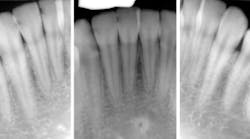

Sydney came in like clockwork every six months for recall. And at every recall appointment, she left with a treatment plan for restorative dentistry. I would start with the upper-right quadrant and work my way through over several weeks after each recall visit. After a couple of years of this, the cycle of rerestoration came full circle, and it was time for me to begin rerestoring teeth that I had worked on before. It was the same story for each restoration: recurrent decay interproximally at the gingival margin and a high plaque index, especially around the resins. At first, I took this poorly. I thought I must have sloppily placed those restorations before. I restored them again—this time bigger—with a rubber dam and moved on.

When Sydney started getting recurrent decay in the same areas around restorations that I had placed with a rubber dam, I began to understand that Sydney was different. I had already known she was different, but I had underestimated just how different she really was. She had the highest caries risk I have ever seen in my career. Three years ago, she moved to Washington, DC, for school. Her parents moved to the East Coast as well, so Sydney has become someone else’s problem.